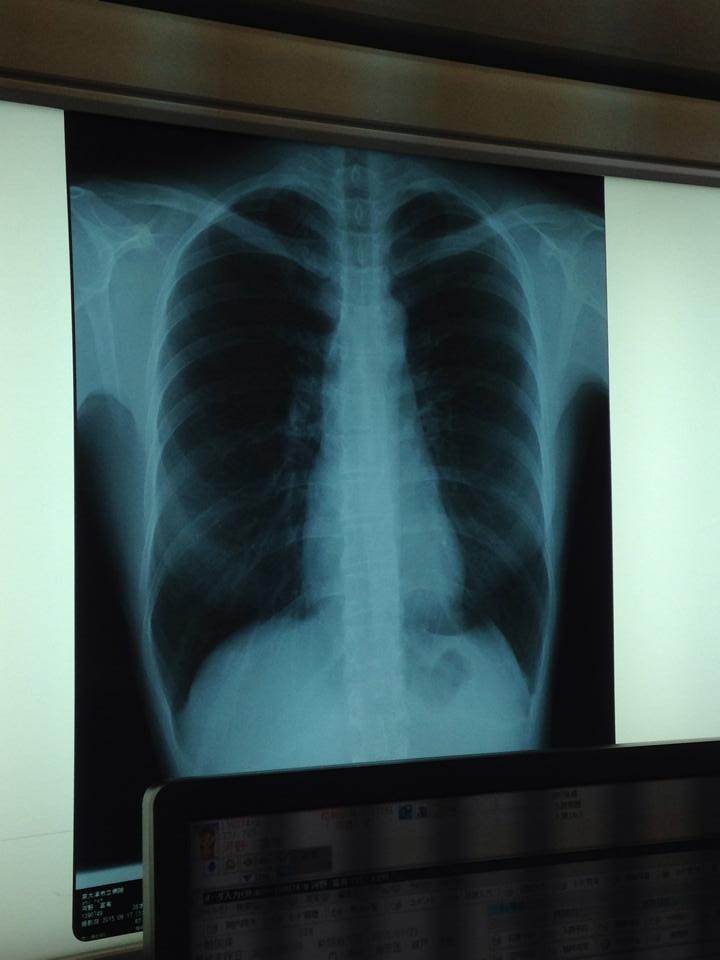

「いえ、それより、喘息関係の咳かなと思いました。実際に、炎症反応も大したこともないそうです。レントゲンも肺炎のような兆候はないし」

「(のどを診て)大丈夫やな。で、レントゲン行こうか」

「レントゲンには、顕著な肺炎も見えないし、CRPもそう高くないから。あまり深刻な状況ではないと思う」